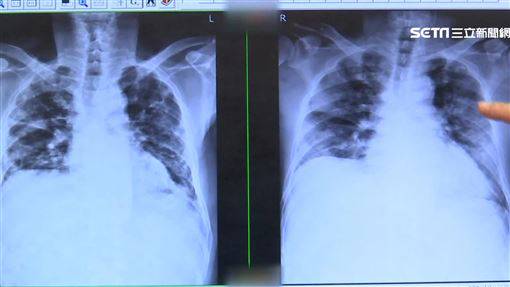

你常忽略咳嗽、喘不過氣等肺部症狀嗎?小心與「肺纖維化」有關。一名建築業高階主管,平時就有咳、喘症狀,但因自認身體還很硬朗而不以為意,也沒有「聽診後背下肺葉」的完整檢查觀念,在一次健康檢查時發現CA19-9指數偏高,誤以為是惡性腫瘤,轉診至胸腔內科才發現肺部已嚴重纖維化,並確診特發性肺纖維化,而後病情很快轉急性惡化,不到一年即病逝。

收治上述個案的台灣胸腔暨重症加護醫學會理事長王鶴健表示,肺纖維化俗稱「菜瓜布肺」,成因非常多元,較為大眾所熟知的有發病原因不明的「特發性肺纖維化」;特發性肺纖維化不可逆,病友易因外部因素刺激導致肺功能急速下降,嚴重者走幾步路就覺得氣喘吁吁,甚至感到呼吸困難。他說,由於疾病進展因人而異且變化多端,若未及早發現並適當治療,五年存活時間比許多癌症還低。

其次,特發性肺纖維化的高危險群應落實「聽診後背下肺葉」的完整檢查。王鶴健說,肺纖維化的發展過程是由肺底往肺尖方向移動、周邊往中心方向蔓延。目前特發性肺纖維化的成因尚不清楚,但50歲以上男性、有吸菸史、肺纖維化家族病史、長期胃食道逆流或是曾暴露於高粉塵環境工作者,都是罹患特發性肺纖維化的高危險族群。王鶴健醫師指出,當肺部開始有纖維化的跡象,醫師在聽診後背下肺葉時,就可聽到有如魔鬼氈撕開的聲音,若有出現「咳、喘、累」三大症狀且已經持續八週以上,儘快到胸腔內科檢查。